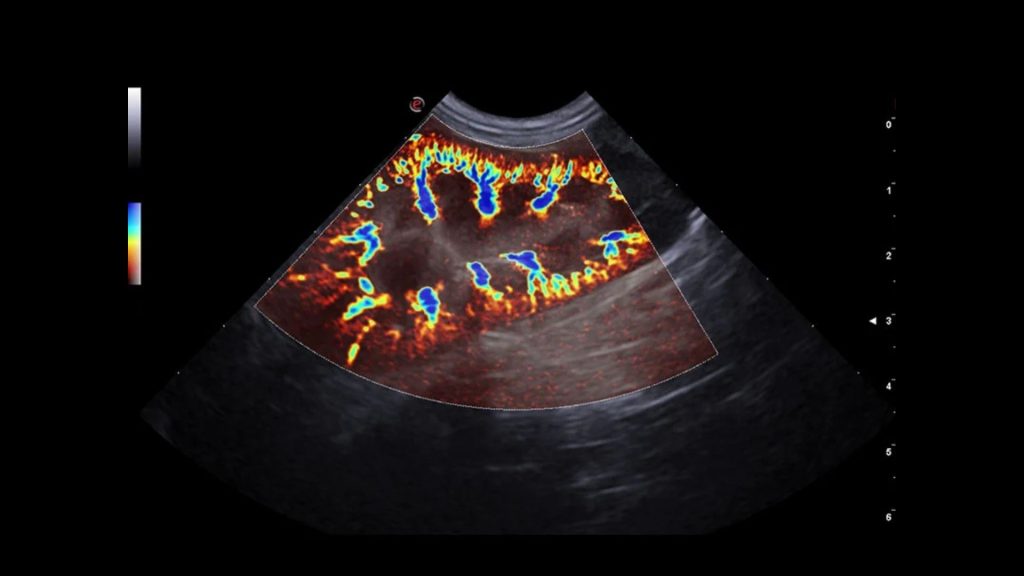

Böbrek ultrasonografisi böbrek fonksiyonuna bağlı olmayan, hasta üzerinde bilinen herhangi bir yan etkisi olmayan, böbrek iç yapısının incelenmesine olanak sağlayan noninvazif bir görüntüleme tekniğidir. Böbreğin ultrasonografik muayenesinde, korteks, medulla ve toplayıcı kanallar görüntülenebilir. Ultrasonografi ile belirlenen böbrek uzunluğu ve hacmi köpeklerde vücut ağırlığıyla doğrusal olarak ilişkilidir. Kedilerde ise ultrasonografi ile belirlenen böbrek uzunluğu 3,0 ila 4,3 cm arasında değişmektedir.

Ultrasonograafik muayene ile tespit edilebilen böbrek hastalıkları; renal kistler, hidronefroz, perinefrik pseudokist, hematom, apse, nekrotik nodüller, tümörler, lenfoma, kronik tubulointerstisyel nefritis, etilen glikol toksisitesi, nefrolitler ve renal agenezidir.

Kan akışına karşı böbrek içi direnç, dubleks Doppler ultrasonografi sırasında değerlendirilebilir ve direnç indeksinin (RI) hesaplanmasıyla değerlendirilebilir.